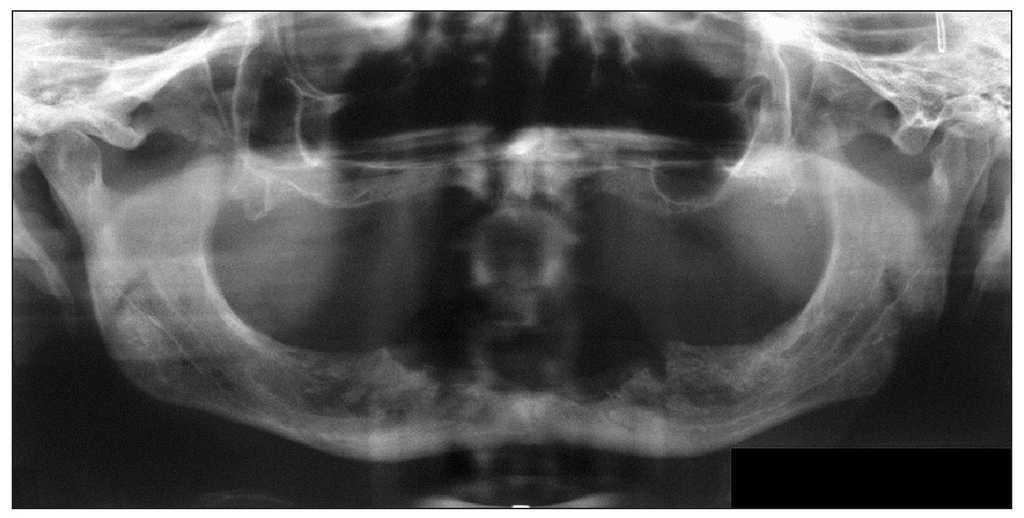

Figura 4c. La radiografía panorámica aporta pocos datos en contraste con el cuadro clínico florido. Además de una imagen radiolúcida difusa en el sector anteroinferior, se observan los alvéolos conservados, a pesar de que la extracción de los dientes se remonta a varios meses atrás. Llaman la atención la radiopacidad y el engrosamiento del periostio.

En las radiografías se aprecia a menudo la persistencia de las paredes corticales de los alvéolos después de las extracciones. Sin embargo, en la fase inicial las imágenes radiográficas a menudo no revelan alteraciones significativas a pesar de un cuadro clínico florido (figs. 5a a 5c). En una fase más avanzada se observan tanto imágenes radiolúcidas difusas como también imágenes radiopacas en las regiones óseas afectadas, pudiendo apreciarse en algunos casos un secuestro o fracturas óseas5.

Figura 5b. Radiografía preoperatoria con imágenes radiolúcidas difusas en el área del hueso expuesto.

Figura 5c. Radiografía postoperatoria después de la eliminación del secuestro, de la eliminación de los bordes óseos afilados y de la extracción de los dientes adyacentes con movilidad grave.